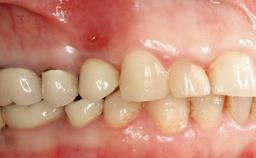

The fracture of an implant after it has been restored is one of the most severe complications. It most frequently occurs in partially edentulous jaws (1.5%). Most implant fractures involve implants with a diameter of 3.75 mm made of commercially pure titanium (Eckert 2010). Unfortunately, many cases are not reported or documented by the clinicians involved in resolving the problems created by the fracture. This case report describes the management of an implant fracture at site 36 in a middle-aged male patient. The implant had been restored with a screw-retained metal-ceramic crown.